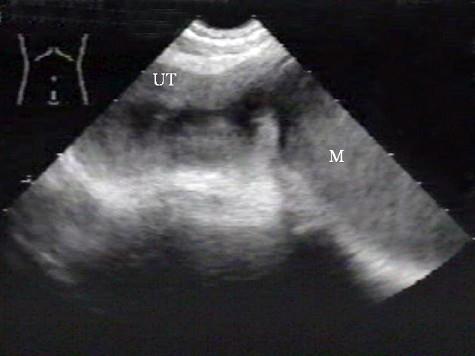

问题 女性,64岁,一周前确诊为宫颈癌。超声检查如图,最可能的诊断是 ( )

选项 A、子宫内膜炎 B、正常声像图 C、宫腔积液 D、子宫内膜癌 E、子宫肌瘤

答案 C